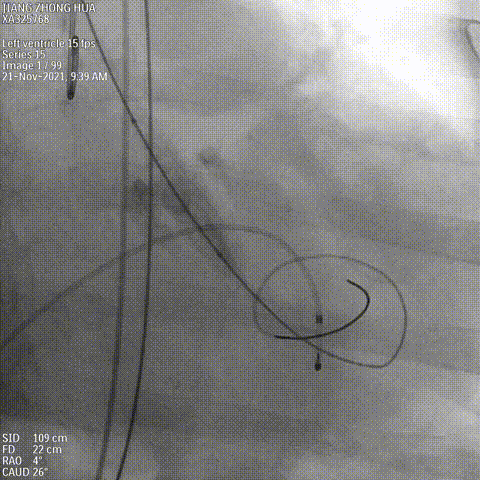

球囊预扩